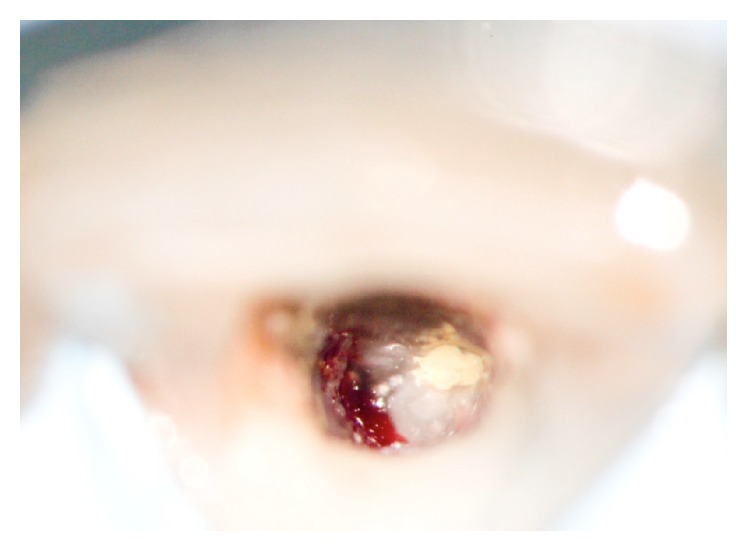

An 18-year-old healthy female patient, initially diagnosed with irreversible acute pulpitis, was referred to our practice after endodontic treatment of her upper central incisor affected by internal resorption had failed. Only the coronary root canal was filled. Radiograph revealed that there was an accidental root perforation present and apical section of the root canal remained unfilled (Figure 4). Internal resorption lacuna was visible in the middle third of the root. Patient's informed consent was obtained prior to endodontic retreatment explaining the rationale for treatment and possible alternatives. The basic requirement in the management of this case was the total removal of resorption granuloma. The procedure was performed under an operating microscope. Access cavity provided a view of the residual resorption granuloma that spontaneously perforated into the periodontal crevice together with failed root canal filling (Figure 5).

Figure 5.

Access cavity with granuloma (left) and failed root filling (right).